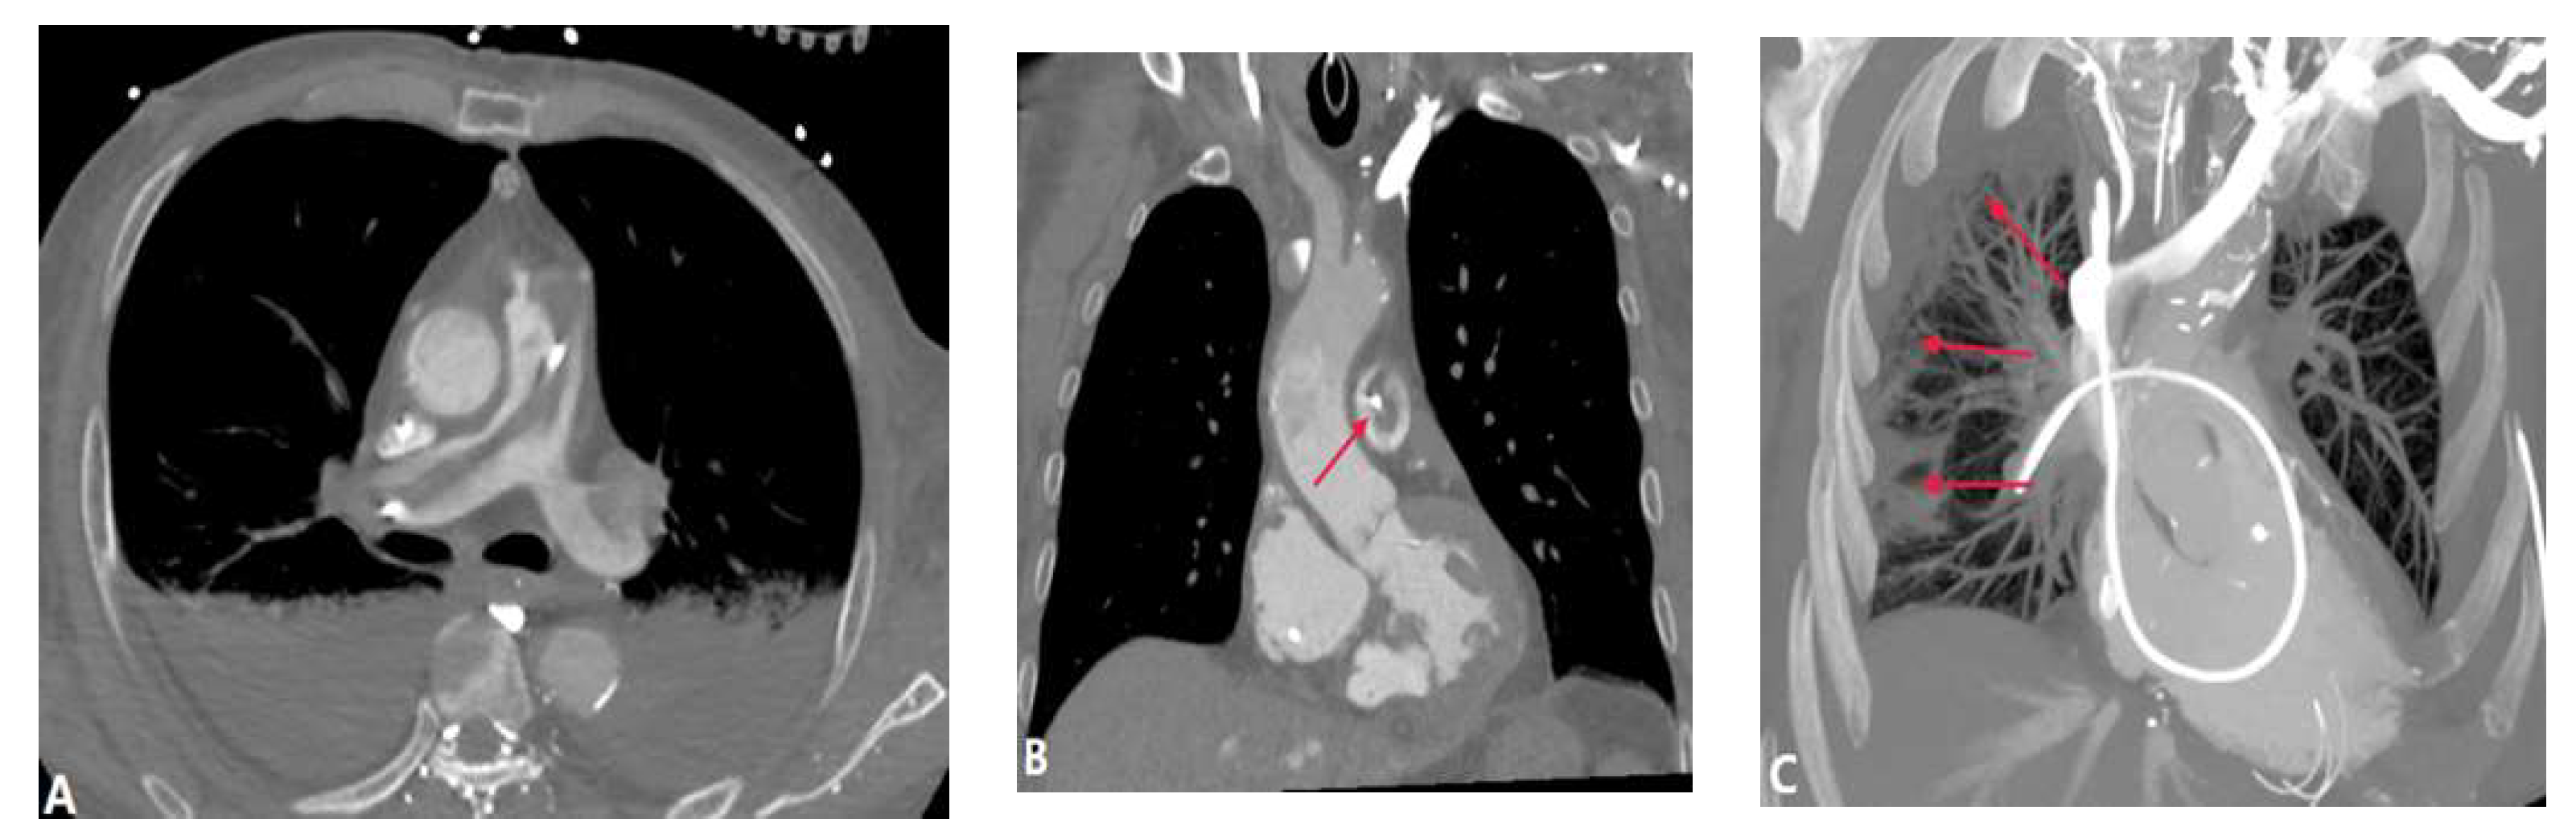

3.1.6. Pulmonary Artery Sarcoma

3.2. Vessel Wall Lesions